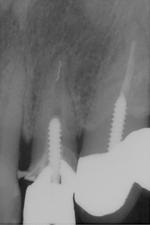

術前 ➡

術後

神経の治療後数年で再発してしまった症例。

根の先までしっかりと薬が入っておらず根の管が細くなってしまっていたのでそれをしっかりと形成し薬を入れました。

保険の治療では根の再感染は避けられないのですが、出来るだけしっかりとした治療を行うと予後が良くなる確率も高くなります。